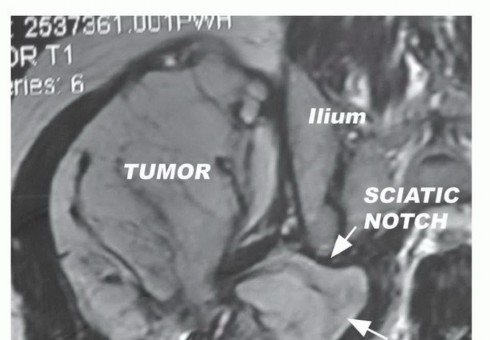

BACKGROUND The gluteus maximus (buttock) is a common site for highand low-grade soft tissue sarcomas. The glu…